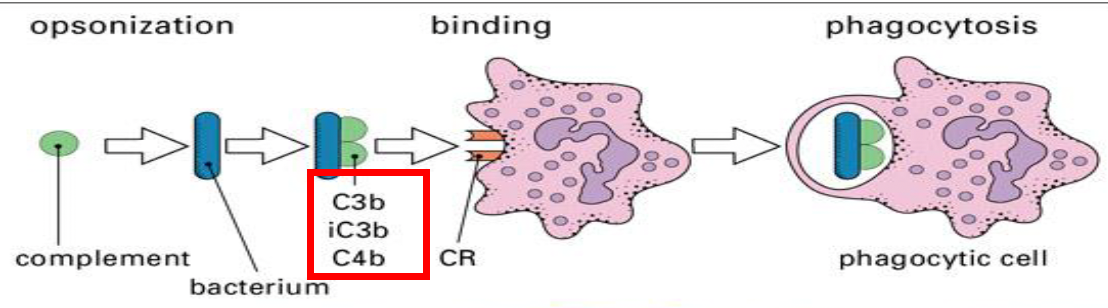

Complement

肝臟製造,血液中

- Lysis 溶解

- Chemotaxis 趨化

- Opsonization 調理

Opsonization 調理

- C3b, C4b

- 結合 Ig

- C3b, C4b

- 結合 Ig

補體受體 (CR)

Factor I 和 CR1 會切斷 iC3b,形成 C3c和 C3dg,而 C3dg 會由CR2 辨認。

- CR1

- 結合 C3b

- 需要 C5a 活化,促進吞噬、調理

- CR2: B cell, EBV(Epstein-Barr virus) receptor

- 結合 C3dg

- CR3, 4

- 認 iC3b

- CR3 是 integrin